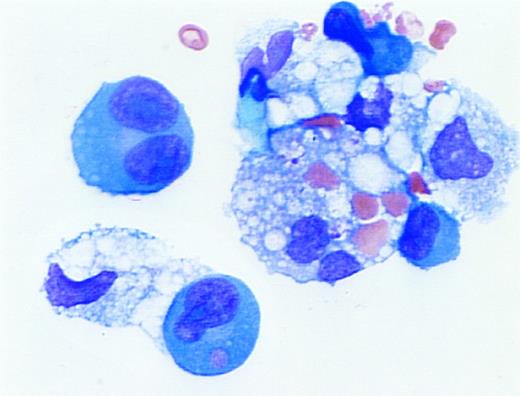

Erythrophagocytosis in myelomatous pleural effusion. A 59-year old woman with advanced multiple myeloma (IgG,κ) and ischemic heart disease presented with congestive heart failure and pancytopenia. A pleural effusion was noted on initial examination and persisted despite diuresis. A diagnostic thoracentesis was performed. The cytospin preparation demonstrated erythrophagocytosis by dysplastic plasma cells and macrophages. (Wright's stain; original magnification ×1,000.) (Courtesy of Larry L. Frase, MD, Joseph Newman, PhD, Martin L. Hurst, MD, and Marvin J. Stone, MD, Baylor-Sammons Cancer Center, Dallas, TX 75246.)